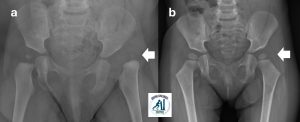

Displasia evolutiva dell’anca

Utilizziamo Tecniche chirugiche moderne e di eccellenza per intervenire sulla patologia “Displasia evolutiva dell’anca“